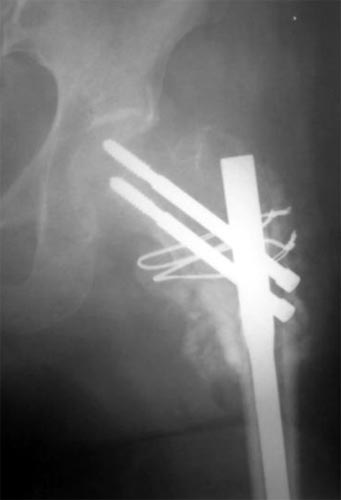

以上图片为三位患者的X线片,显示股骨粗隆下骨折、骨不连,内固定已经失败。

主要采用股骨重建髓内钉获得良好早期的稳定性,为骨愈合创造条件,

有的病例采用DHS治疗,同时采用骨髓细胞和植骨复合物植入。成功治愈患者。